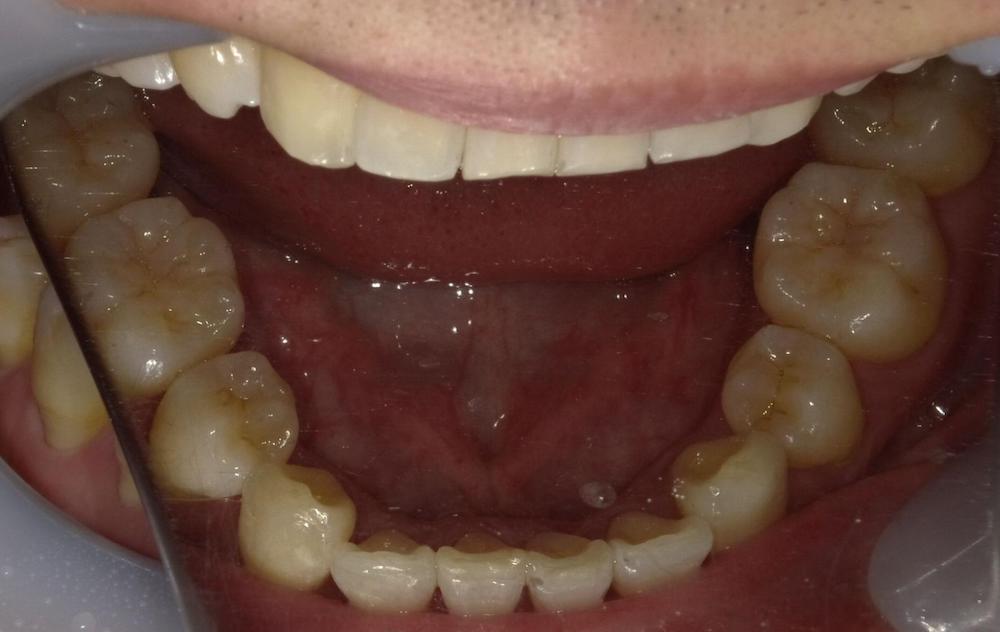

症例2 舌癖による後戻りケース (軽度)

舌を前歯に押し付ける癖があり、徐々に前に出てきてしまったため再矯正を行いました。矯正中から舌トレーニングを行い舌癖の改善に努めました。

- 治療方法 :インビザラインエクスプレス上下

- 治療期間 :6ヶ月

- 治療費用:¥385000(税込)

- 治療のリスク・デメリット :舌癖の改善をする必要がある

Before

After